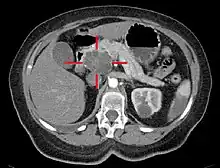

Medical imaging techniques, such as computed tomography (CT scan) and endoscopic ultrasound (EUS) are used both to confirm the diagnosis and to help decide whether the tumor can be surgically removed (its "resectability").[12] On contrast CT scan, pancreatic cancer typically shows a gradually increasing radiocontrast uptake, rather than a fast washout as seen in a normal pancreas or a delayed washout as seen in chronic pancreatitis.[55] Magnetic resonance imaging and positron emission tomography may also be used,[2] and magnetic resonance cholangiopancreatography may be useful in some cases.[31] Abdominal ultrasound is less sensitive and will miss small tumors, but can identify cancers that have spread to the liver and build-up of fluid in the peritoneal cavity (ascites).[12] It may be used for a quick and cheap first examination before other techniques.[56]